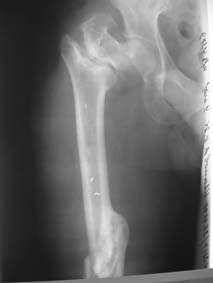

> Уважаемые коллеги! Нужен совет. Больной Х., 21 год, ДЗ: ложный сустав вертельной области

> правого бедра. Травма 8 мес. назад, ДТП, получил закрытый межвертельный перелом правого

> бедра. Лечился в городской больнице одного из городов-спутников г. Караганды скелетным

> вытяжением в течение 3 недель, затем кокситной гипсовой повязкой 2 мес.

> В настоящее время имеется укорочение конечности на 7 см, умеренная

> боль в вертельной области; ходит без костылей, полностью нагружая

> больную конечность, при нагрузке отмечается смещение дистального

> отломка проксимально примерно на 1,0 см.; объем движений в коленном

> суставе сохранен; при пальпации отломков боли нет, умеренная

> патологическая подвижность.